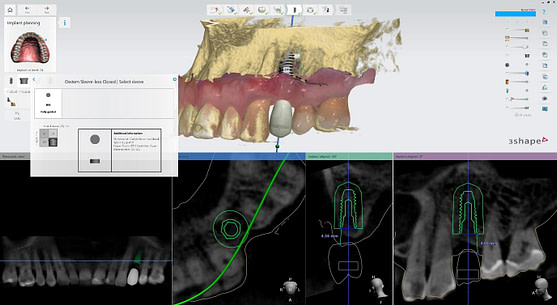

Pre-surgical planning began with acquiring high-quality diagnostic data, including TRIOS intraoral scans and CBCT imaging. The data was imported into 3Shape Implant Studio, where I designed a virtual crown for tooth 24 and planned the precise positioning of the implant, considering critical factors such as sinus proximity, adjacent roots, bone density, and the location of the bony defect.

A custom surgical guide was designed and 3D printed, incorporating all the critical information from the virtual planning. The implant surgery was performed under local anesthesia, with the surgical guide firmly in place to ensure accurate implant placement. Bone grafting was performed to address the bony defect and promote optimal healing.

The Osstem OneGuide kit is used with a fully guided osteotomy and implant placement.

Osstem TSIII D4 x H10mm implant on NoMount driver.